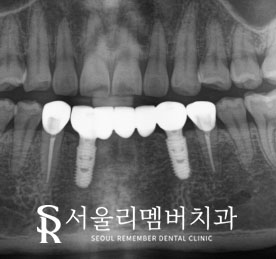

- 최종 보철물 장착

2개월 뒤

인공치근과 치조골이 단단히 유착됐다면

이후에는 최종 보철물을 올려주면 됩니다.

환자가 구강위생관리를 보다

편하게 하실 수 있도록

송곳니와 작은 어금니는

각각 지르코니아 크라운으로 제작하였고,

아래 앞니 브릿지는 맞춤형으로 제작하였습니다.

그런데 사진에서 보면 보철물 안쪽에

동그란 구멍이 있는데요,

이는 임플란트의 유지 보수를 위한

'홀(hole)'입니다.

저 홀을 통해 브릿지를 꼈다 뺐다 하면서

세척을 하거나

추후에 보철이나 픽스처에

문제가 생겼을 때 교체할 수 있습니다.

인공치근은 턱뼈 안에 단단히 심어져 있지만

그 위로 나와있는 보철물은

하루에도 수천 번씩 맞물리고

움직임을 받기 때문에

꼭 필요한 구멍이랍니다.

브릿지의 색깔과 디자인이 마음에 들었다면

저 홀들은 상아색의 레진으로 막아드릴 예정이라

눈에 보이거나 티가 나지는 않습니다.

- 마무리

서울대입구역 치과 에서

내려간 잇몸 라인에 맞추어

최종 보철물을 장착한 모습입니다.

정말 자연스러워서

환자도 많이 만족해하셨습니다.

특히 임플란트는 2개밖에 심지 않았는데

치아는 총 5개가 만들어진 부분에 대해서